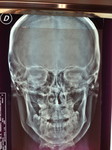

Paziente candidato a intervento di chirurgia Ortognatica